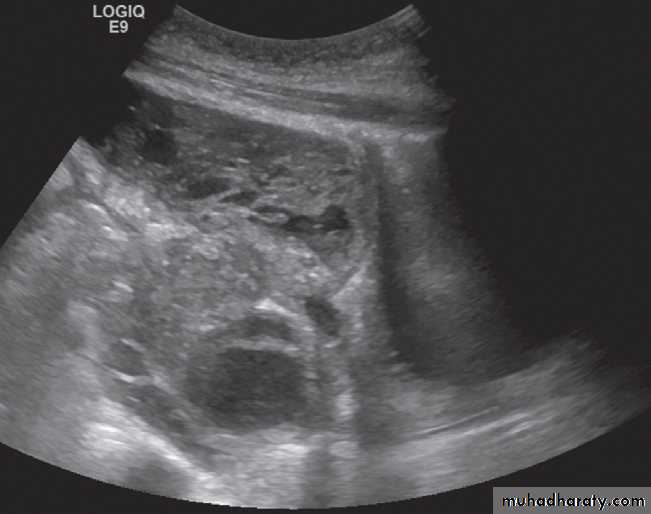

At ultrasound

Endometriosis is usually seen as a cystic mass with homogeneous internal echogenicity in the adnexal region and/or pouch of Douglas corresponding to the chocolate cysts found on pathological examination .

On MRI There are characteristic appearances due to recurrent haemorrhage into endometriomas and there is often in-drawing of the rectum towards the pouch of Douglas due to the development of fibrous adhesions.